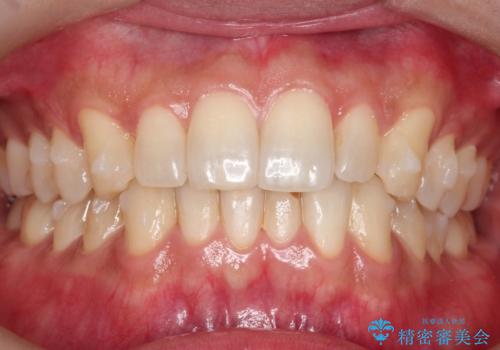

初診時の歯並びの状態としては、下顎に中等度のがたつき(叢生)がある状態でした。

抜歯は行わず下顎の奥のスペースを利用して歯をスライドする方法の他に親知らずの抜歯そして上下ともに歯列弓の拡大やディスキング(歯と歯の間の隙間を作る処置)を行い叢生を改善しました。

歯の大きさの不揃いが原因の正中のズレは、ディスキング量を調整することで合わせました。